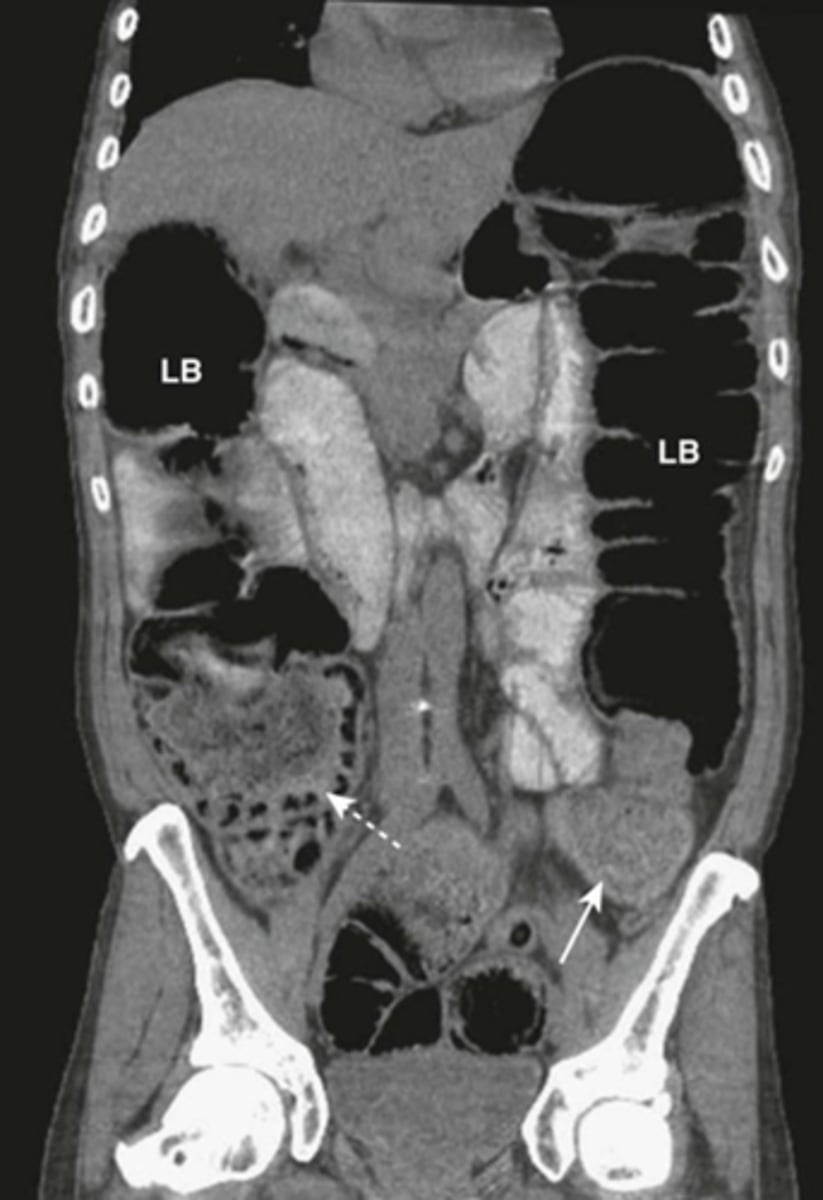

Partial SBO.

SOLID WHITE ARROWS: dilated and contrast containing loop of small bowel

DOTTED WHITE ARROWS: air in collapsed colon

Coronal-reformatted CT with oral contrast shows dilated and contrast-containing loops of small bowel. Although there is still air in the collapsed colon, the disproportionate dilatation of small bowel identifies this as a small bowel obstruction.